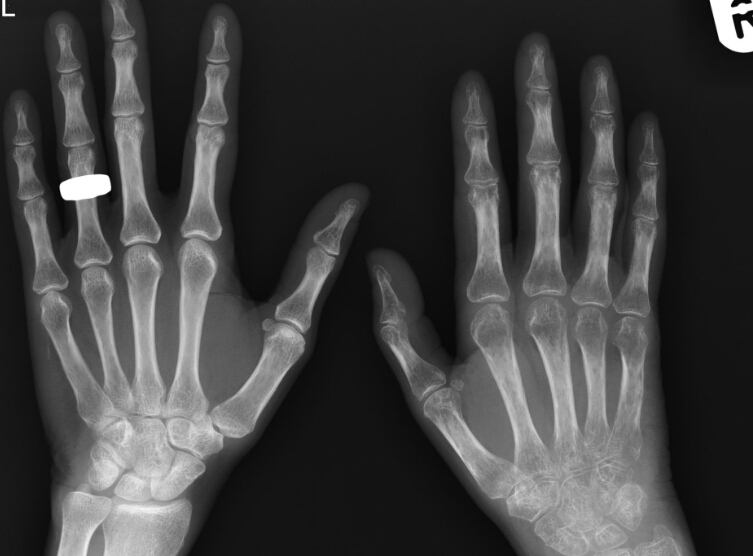

What is the diagnosis? What makes you think so?

Reflex sympathetic dystrophy

there is pretty severe demineralization and the joint spaces are good